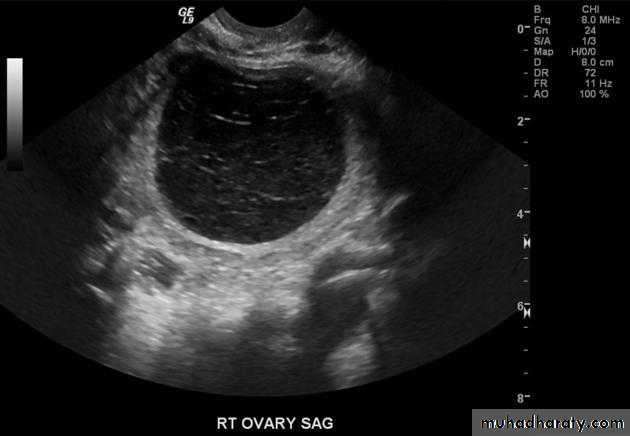

Ovarian cysts :

Ovarian cysts are commonly encountered in gynecological imaging, and vary widely in etiology, from physiologic, to complex benign, to neoplastic.Small cystic ovarian structures should be considered normal ovarian follicles unless the patient is pre-pubertal, post-menopausal, pregnant, or the mean diameter is >3.0 cm

Radiographic features

Ultrasound is usually the first imaging modality for assessment of ovarian lesions. Simple ovarian follicular cysts are:

anechoic

intraovarian or exophytic;

have an imperceptible wall